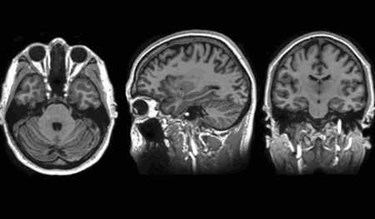

The new system, which already is installed at the Mayo Clinic’s downtown campus in Minnesota, uses a superconducting 3T magnet, a new prototype that is one-third the size of MR magnets and requires a smaller amount of liquid helium to operate, as well as less electricity. The system can be used to perform head scans as well as scans of smaller extremities, such as hands and feet, according to a press release.

“A lot of team work went into the development, construction, and fine-tuning of the machine, and even more will go into determining the full scope what physicians are able to do with it to improve patient outcomes and experiences,” said Matt Bernstein, a medical physicist in the Mayo Clinic’s Department of Radiology, to Discovery’s Edge. “The smaller design actually permits increased scanner performance, because both the electrical power requirements and physiological limitations imposed by a whole-body MRI scanner are greatly reduced.”